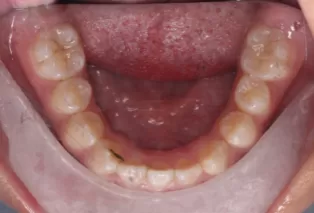

Intraoral photos